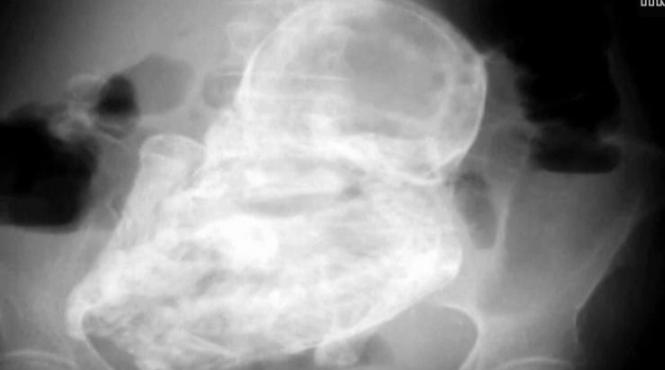

Descoperire INCREDIBILĂ, făcută de medicii din Bogota. Ce au găsit specialiştii în abdomenul unei femei de 82 de ani (VIDEO)